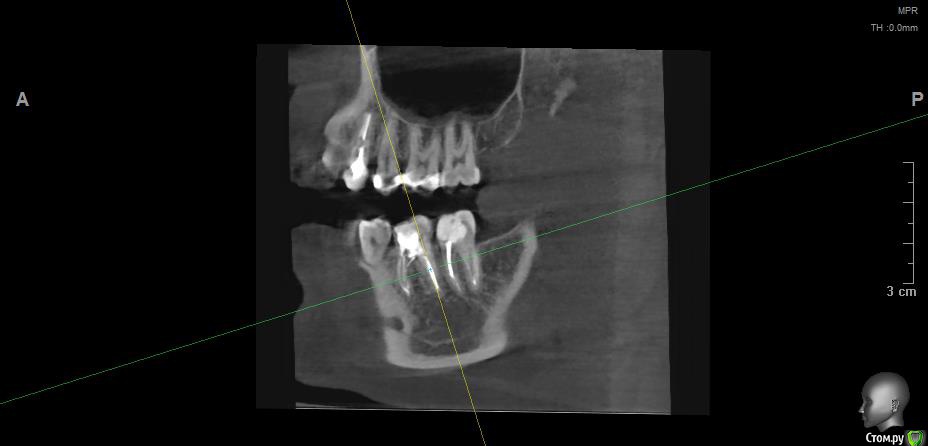

Vords Опубликовано 11 июня, 2020 Поделиться Опубликовано 11 июня, 2020 (изменено) Доброго вечера, профессионалы. Прошу у Вас помощи. Буду очень благодарен за консультацию. 3 недели назад появились боли в в жевательных зубах (около 37 и 36 зубов). В виду того, что боли были достаточно серьезные, а врач, у которого я лечился ранее не мог меня принять из-за пандемии - пришлось идти в городскую поликлинику. По результатам похода был поставлен диагноз пульпит 37 и глубокий кариес 36. На 36 поставили пломбу - 37 успешно депульпировали. На этом история 37 зуба закончена. С 36 после постановки пломбы начались дикие ночные боли и боли при накусывании. На повторном приеме был поставлен диагноз пульпит 36 - поставлено лекарство для умертвления нерва. После этого боль при накусывании прошли. В следующий прием пришел на чистку каналов и пломбировку. Во время этой процедуры я вдруг ощутил совершенно дикую боль (как выяснилось потом - в этот момент и произошла перфорации в области фуркации). Врач ничего не сказал - просто поставил метапекс и запломбировал каналы. В этот момент начались боли при накусывании. а потом постоянная тянущая боль. Продолжалось это около 3 дней - я пошел в другую стоматологию где мне сделали рентген и с подозрение на перфорацию отправили на КТ. По результатам КТ перфорация была подтверждена. С КТ я пришел в городскую стомотологию где мне предложили закрыть перфорацию цементом (pro что-то там - не могу сказать точно). Закрыли ее во вторник на этой неделе. Сегодня восстановили коронку и поставили световую пломбу. Беда в том, что боль при накусывании и "нытье" с этой стороны так и не прошли. По словам стомотолага гос клиники - боль при накусывании из-за метапекса и когда он рассосется - боль пройдет. (до 6 месяцев). Я прилагаю рентген (ужасное качество), фото КТ и ссылку в облако на КТ. Я допускаю, что никто не захочет лезть в облако и тратить свое время на просмотр на КТ (сам не могу разобраться с программой, что бы сделать достойные скрины), но если вдруг у кого-то найдется время - буду очень благодарен. Рентген сделан сразу после пломбировки канала. КТ через 3 дня после этого. В связи с этим вопрос. Возможно ли, что боль при надавливании пройдет если подождать пока рассосется метапекс или это пустая трата времени? Мне стоит ждать какое - то время или в этой ситуации мне поможет только удаление? Благодарю Вас за уделенное время Ссылка на КТ https://cloud.mail.ru/public/44WE/2JeTfXmr2 Изменено 11 июня, 2020 пользователем Vords Ссылка на комментарий

krokomot Опубликовано 11 июня, 2020 Поделиться Опубликовано 11 июня, 2020 Судя по всему у вас в 6м зубе выведен не только метапекс но и гуттаперчевый штифт, скорее всего, если это не исправить боли сохранятся, и что там с коронкой не понятно, на кт сильные тени из-за большого объема рентгеноконтрасного материалла, а прицельный снимок что вы сделали, сделан не поп правилам и на нем сильные искажения, понять трудно что с коронкой. Короче, зуб с перфорацией , выведенным материалом за апексом и гуттаперчей, и при этом еще и беспокоит, прогноз сомнительный. возможно всё можно переделать и всё станет нормально , но это не точно. Вам нужен грамотный доктор эндодонтист. 1 Ссылка на комментарий

wladdX Опубликовано 11 июня, 2020 Поделиться Опубликовано 11 июня, 2020 (изменено) Скриншоты Изменено 11 июня, 2020 пользователем wladdX 1 Ссылка на комментарий

Vords Опубликовано 11 июня, 2020 Автор Поделиться Опубликовано 11 июня, 2020 (изменено) WladdX, огромное спасибо Вам за потраченное на скрины время. А то я так и не смог освоить эту программу (рукалицо). У меня даже есть ощущение, что я вижу теперь штифт, о котором говорил krokomot (хотя и не факт)))) Изменено 11 июня, 2020 пользователем Vords Ссылка на комментарий

krokomot Опубликовано 12 июня, 2020 Поделиться Опубликовано 12 июня, 2020 Да есть 2 Ссылка на комментарий